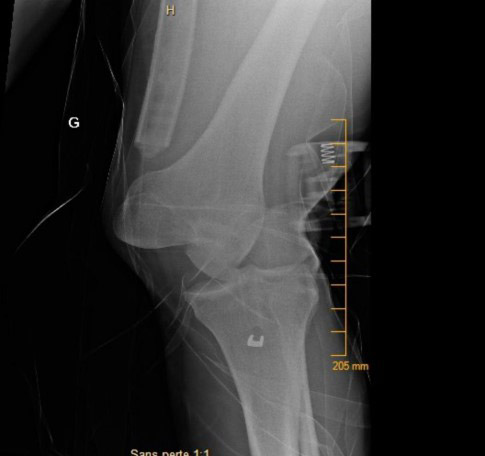

X-Ray at his arrival to the ER